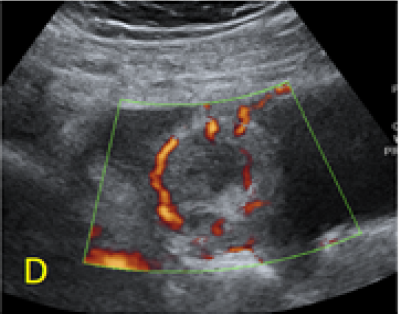

A 22-year-old secundigravida, presented to our Hospital with acute pelvic pain and vaginal bleeding. Her medical history included a 2-year prior caesarean delivery. The patient was in a stable condition and the clinical exam was unremarkable. As the urinary pregnancy test was positive, a transvaginal ultrasound scan was performed to evaluate the pregnancy location and viability. The exam revealed an empty uterine cavity but identified the gestational sac at the level of the caesarean scar with a live embryo (174 beats per minute), measuring 8 weeks and 5 days by crown-rump length. (Figures 1). Because the trophoblastic tissue was noted with an anteriorly location, urinary bladder invasion was suspected based on the ultrasonographic signs: poor identification of the bladder wall, the lack of the sonolucent space and increased vascularization with abnormal pattern (Figure 2). The patient blood tests results were normal, and beta-human chorionic gonadotropin (b-HCG) value was 145.000mUI/ml. After proper counselling and written informed consent the patient opted for a medical conservative treatment with desire to preserve her fertility.

Figure 2. A, B: empty uterine corpus and the presence of the gestational sac at the level of the previous cesarean scar, transabdominal assessment. C, D, E: Same approach, evidence of bulging of the gestational sac into the urinary bladder, with hypervascularity highlighted using Power Doppler evaluation.